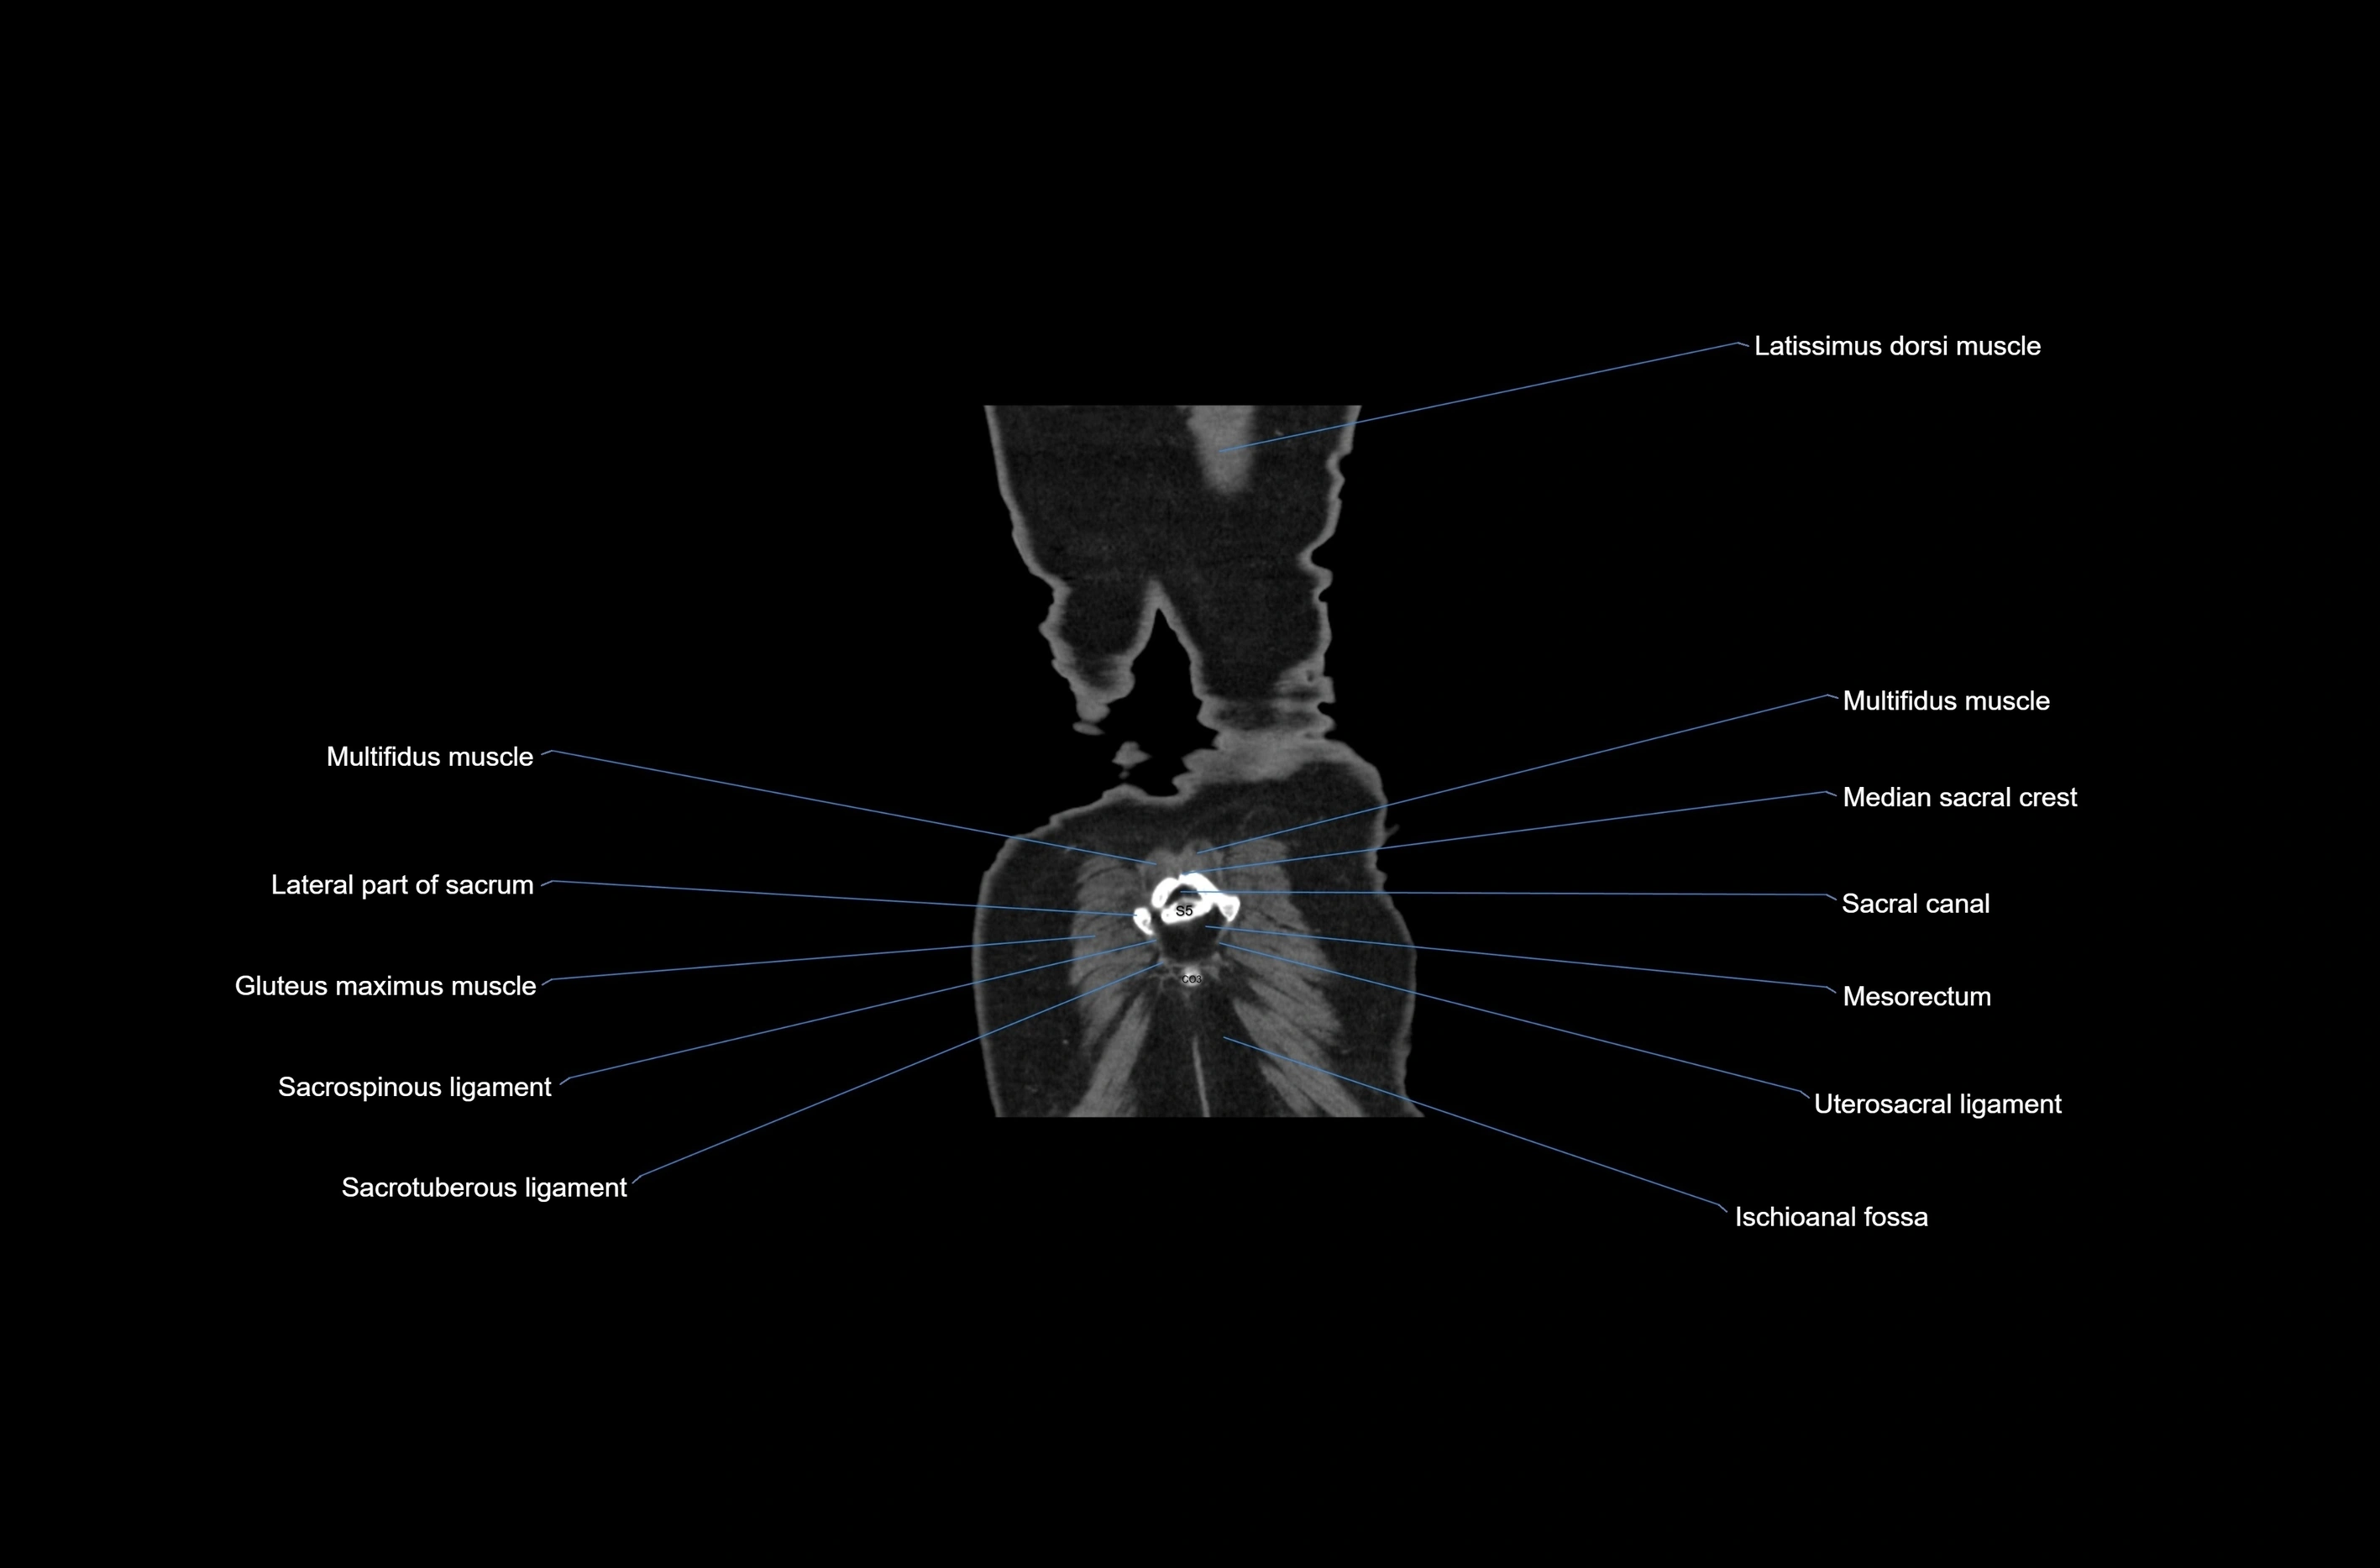

CT images